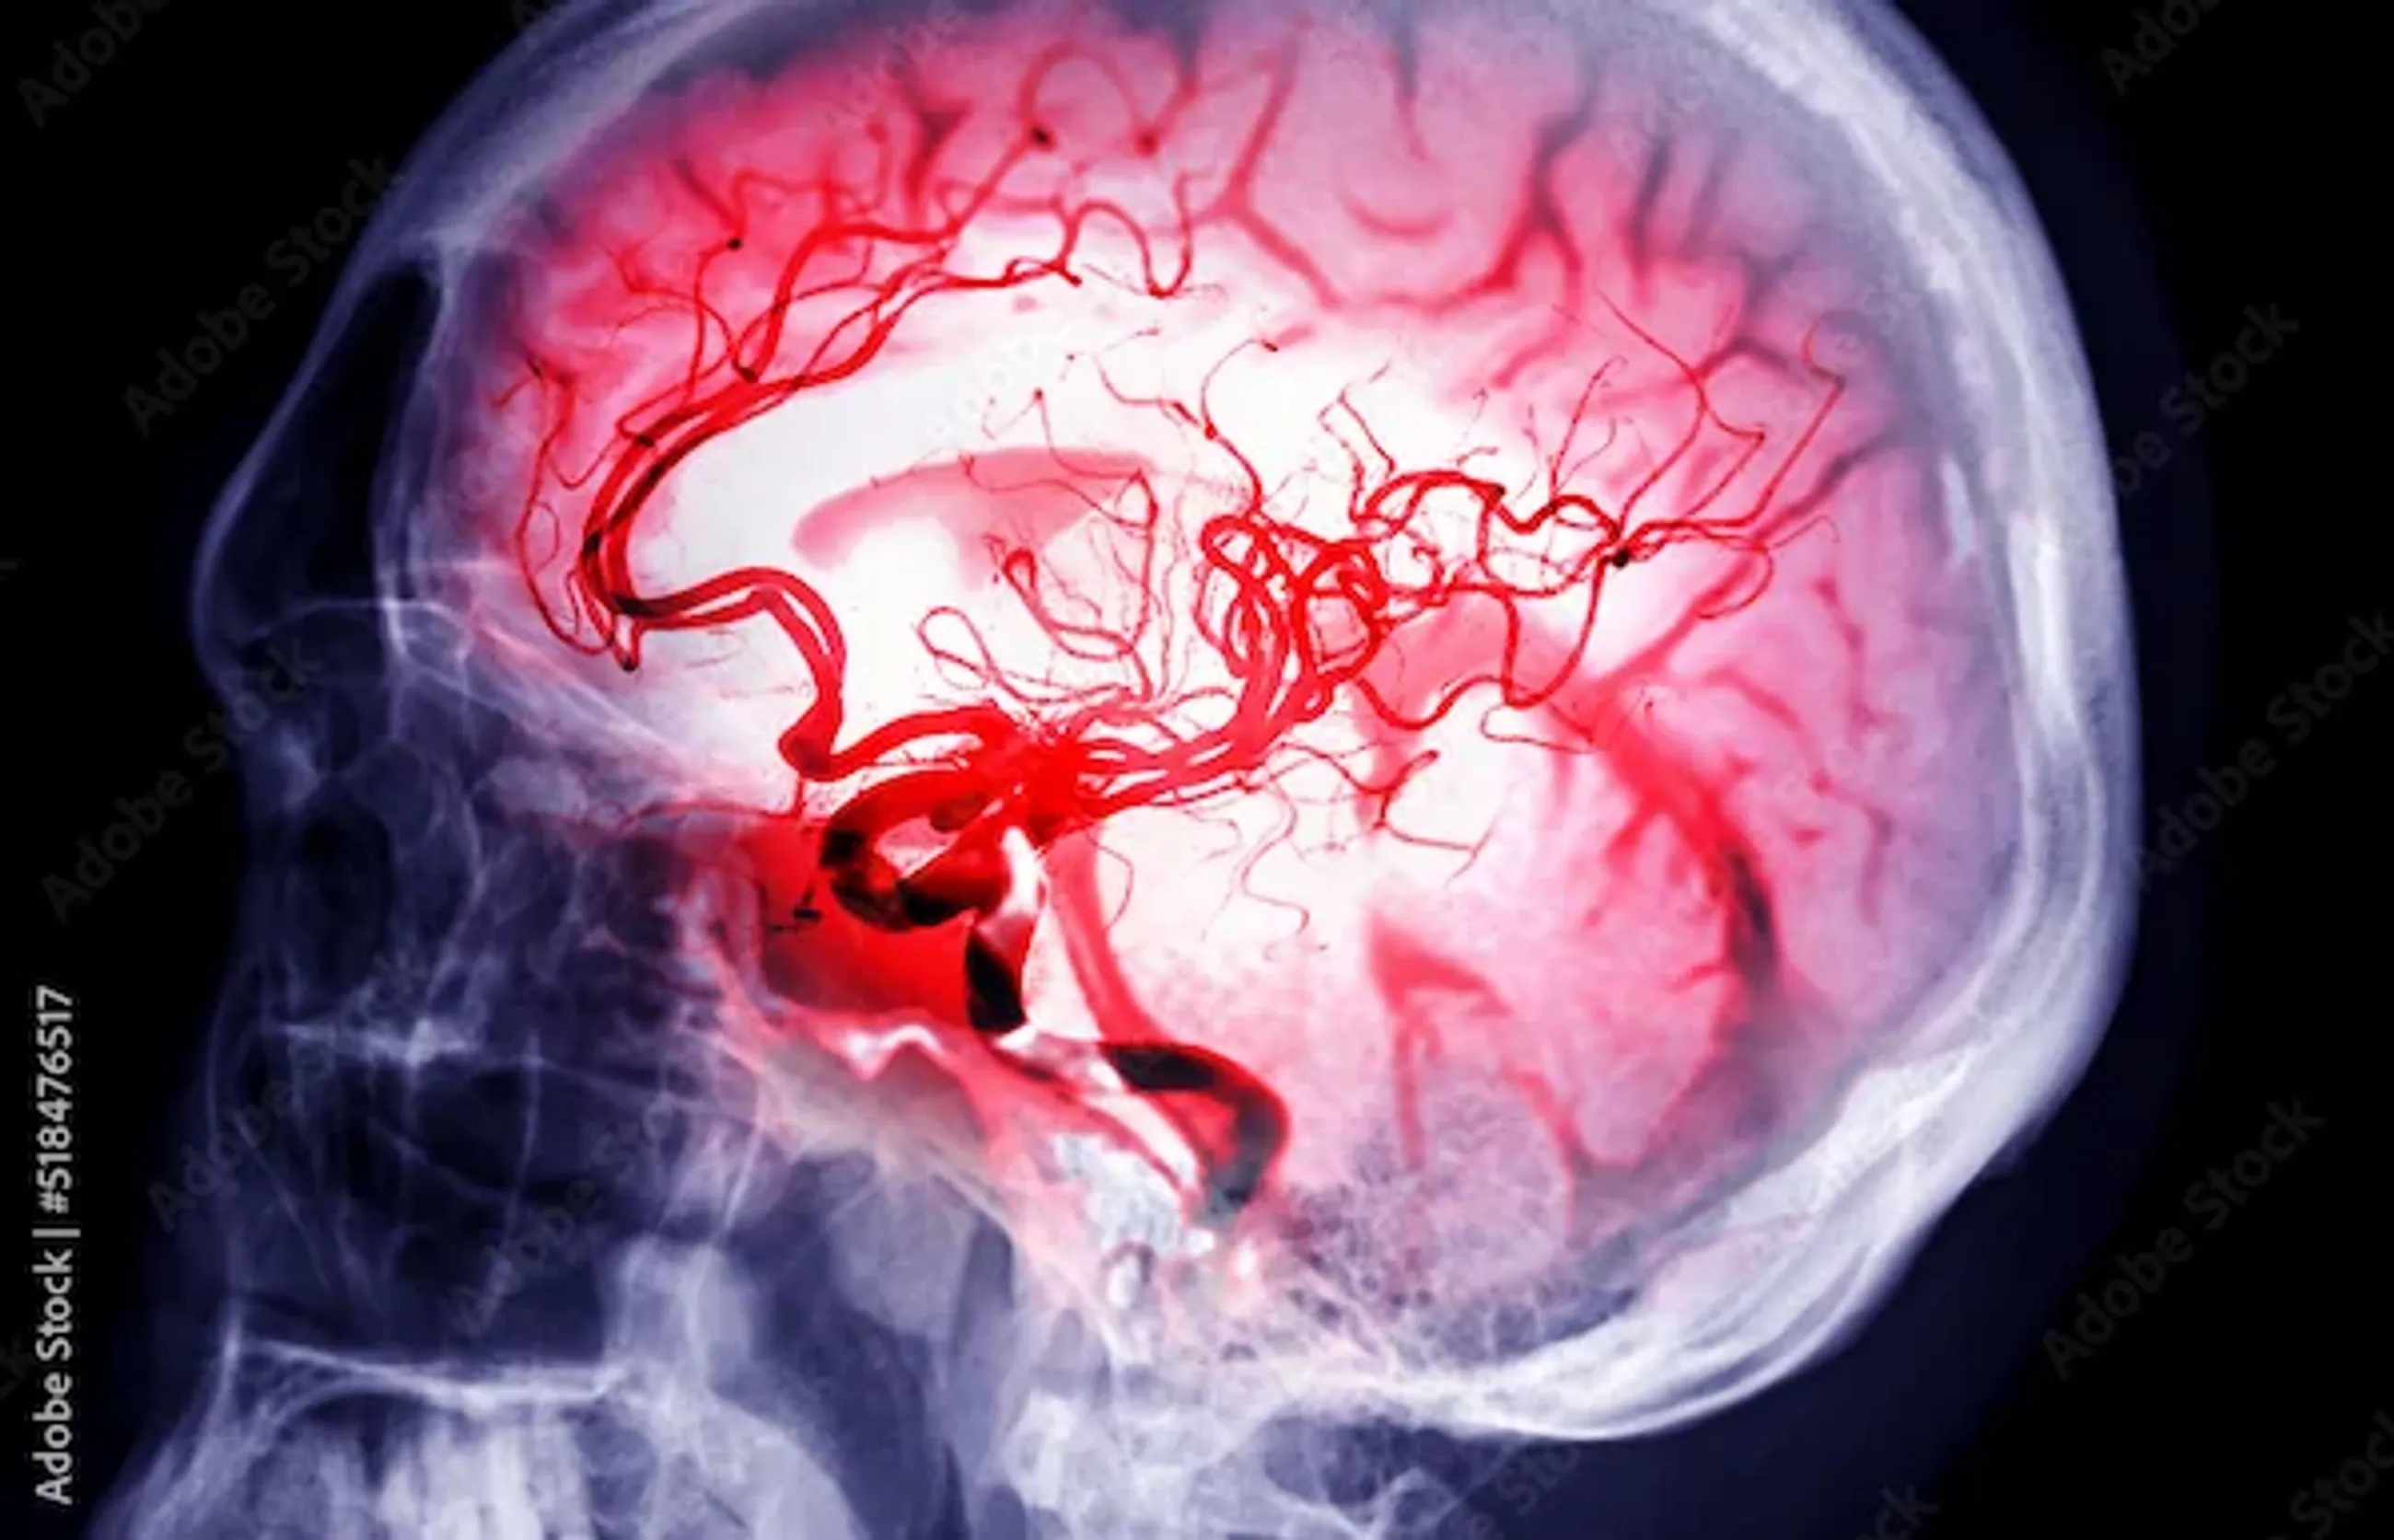

A stroke happens when the blood supply to part of the brain is interrupted or reduced, depriving brain cells of oxygen. Due to lack of oxygen, brain cells begin to die, and this can lead to permanent damage. There are two main types of strokes:

Ischemic Stroke: The most common type, caused by a blockage in a blood vessel which supplies blood to the brain.

Hemorrhagic Stroke: Occurs when a blood vessel in the brain ruptures, causing bleeding in or around the brain.